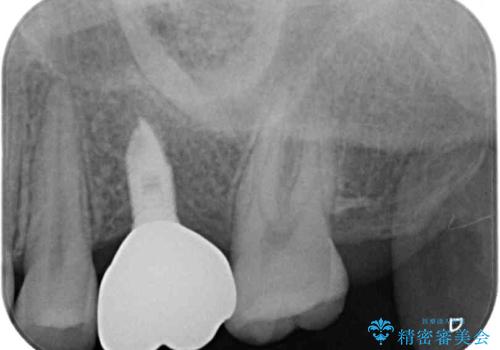

インプラントによる補綴治療とインビザライン矯正

- 抜歯が必要と診断された奥歯を気にして来院された患者様です。

抜歯の上インプラントによる補綴治療を行うこととなりましたが、前歯の叢生も気になるとのことで並行して矯正治療を行うこととしました。

歯列不正は軽微であったので、インビザラインによる矯正治療とし、矯正治療中にインプラント埋入を行う予定としました。

痛みがないので、ボロボロのまま放置していましたが、抜歯後は汚れが溜まりにくくなりスッキリとしたようです。